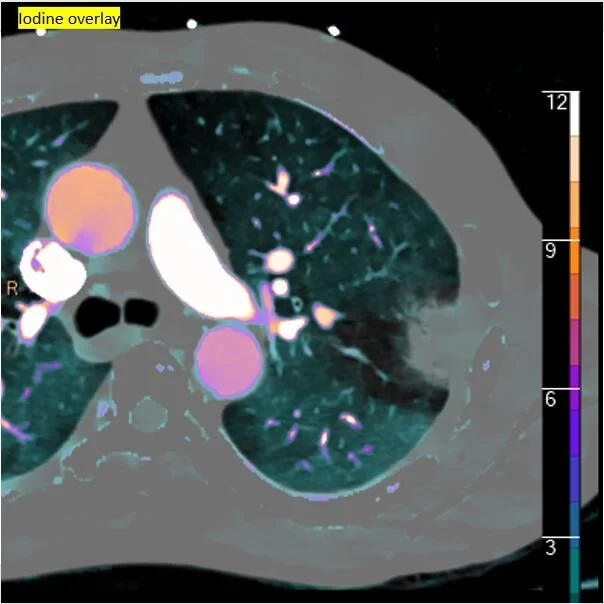

Iodine map shows infarct is the core of the large perfusion abnormality

Iodine overlay: The infarct is a lot smaller than the perfusion abnormality